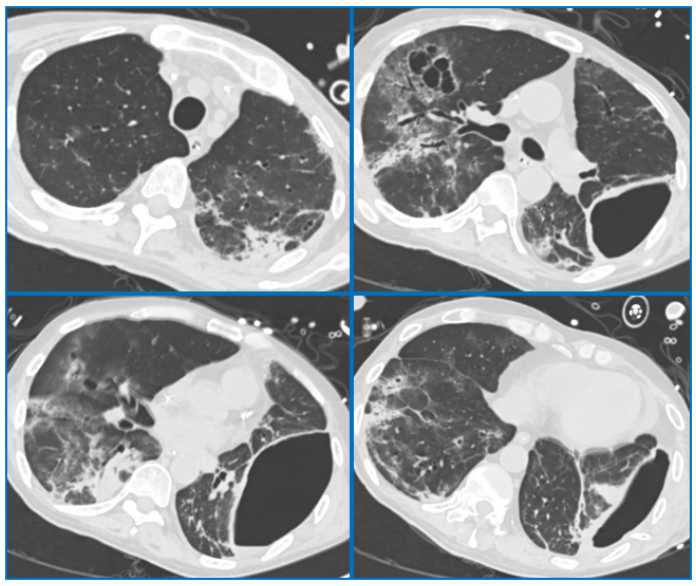

影像学:2023年12月27日床旁胸片示:右肺和左肺上叶透亮度明显下降,大片实变和渗出;左肺下叶有空泡影(图1)。ECMO上机第3天复查胸部CT示双肺多发渗出和实变,左肺下叶有脓腔形成(图2)

图2  患者ECMO上机第3天胸部CT

ECMO撤机第2天复查胸部CT可见双肺多发实变、渗出较前明显吸收,脓腔较前明显缩小(图4)

图4  ECMO撤机第2天患者胸部CT